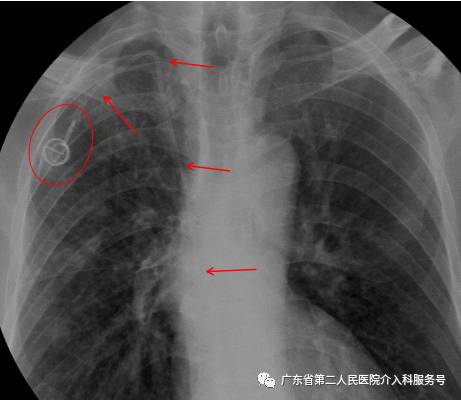

E.右侧乳腺癌或右锁骨下静脉因各种原因不能穿刺者,可以在超声引导下穿刺左锁骨下静脉行输液港植入